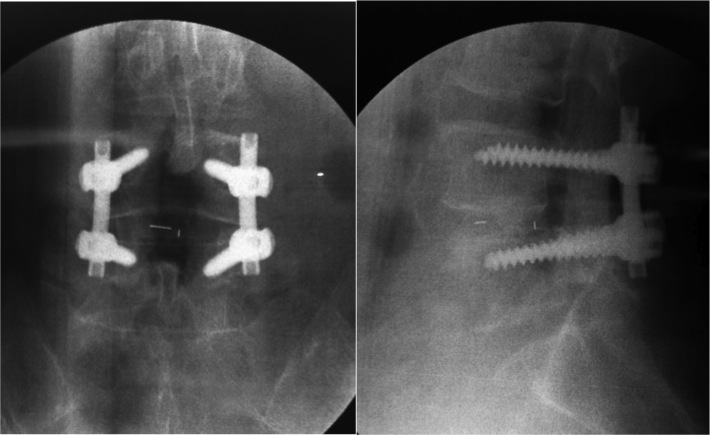

然而,經過臨床檢查,我發現他的病是由退化性腰椎椎體滑脫而引起的嚴重椎管狹窄。由於可以確定神經受壓的地方,再加上他的身體狀況及骨質密度都良好,所以我建議他動手術進行神經減壓及椎體融合去醫治。當然手術不可能令病人重返年輕時的體質與狀態,但是至少可以幫他減輕疼痛及改善生活素質。

■做完減壓及融合後的X光,只有利用外科手術才可將椎體滑脫復位。